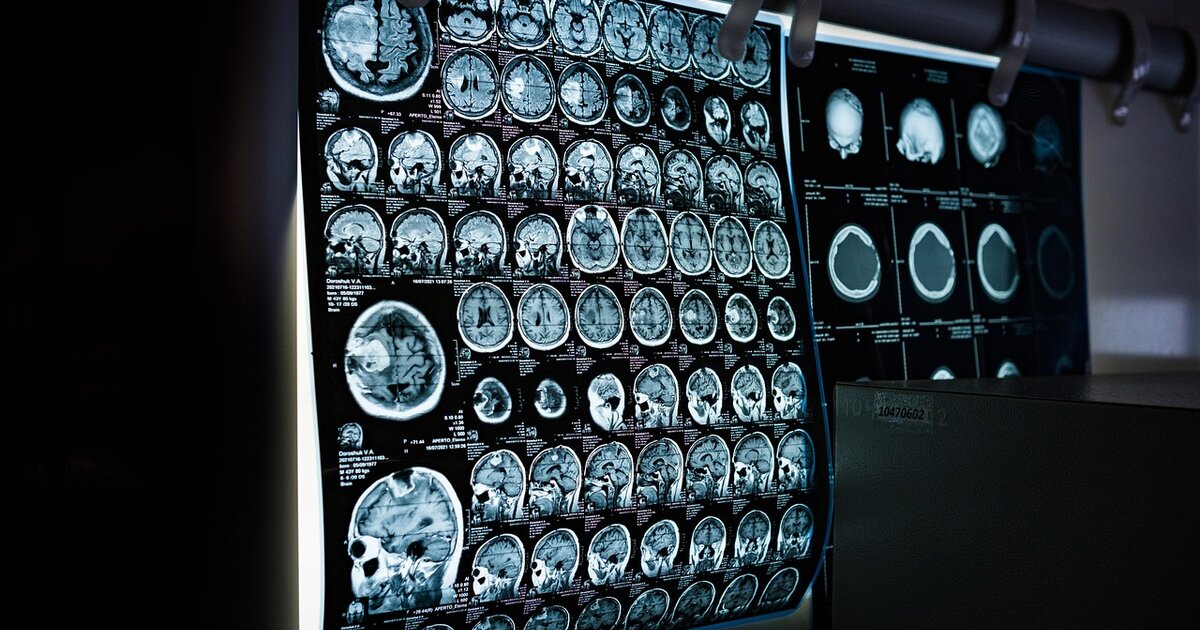

Νέα ανάλυση σε τομογραφίες εγκεφάλου εντοπίζει τις λεπτές ανατομικές μεταβολές που μπορούν να προειδοποιήσουν έγκαιρα για την πάθηση - Ποιες οι διαφορές ανά φύλο

Η τεχνητή νοημοσύνη μπαίνει ολοένα και συχνότερα στο πεδίο της νευροαπεικόνισης, με στόχο να εντοπίζει πρώιμα σημάδια νευροεκφυλισμού πριν αυτά γίνουν σαφή στην κλινική εικόνα. Σε αυτή την κατεύθυνση κινείται νέα μελέτη ερευνητών του Worcester Polytechnic Institute (WPI) που δημοσιεύθηκε στο Neuroscience, η οποία αναφέρει ότι μοντέλο μηχανικής μάθησης μπορεί να προβλέψει τη νόσο Αλτσχάιμερ με ακρίβεια 92,8%, αναλύοντας ανατομικές αλλαγές στον εγκέφαλο από μαγνητικές τομογραφίες.

Η ερευνητική ομάδα αξιοποίησε δεδομένα από την Alzheimer’s Disease Neuroimaging Initiative (ADNI), μια πολυκεντρική βάση με απεικονιστικά και κλινικά στοιχεία. Εξετάστηκαν 815 μαγνητικές τομογραφίες εγκεφάλου ατόμων ηλικίας 69 έως 84 ετών, που ανήκαν σε τρεις κλινικές κατηγορίες: φυσιολογική γνωστική λειτουργία, ήπια γνωστική διαταραχή και νόσο Αλτσχάιμερ.

Αντί να τροφοδοτήσουν το μοντέλο με αυτούσιες εικόνες, οι ερευνητές προχώρησαν πρώτα σε ποσοτικοποίηση. Υπολόγισαν τις μετρήσεις του όγκου σε 95 εγκεφαλικές περιοχές και κατόπιν χρησιμοποίησαν αλγόριθμο μηχανικής μάθησης, ώστε να ταξινομήσει τα περιστατικά βάσει των διαφορών στις μετρήσεις.